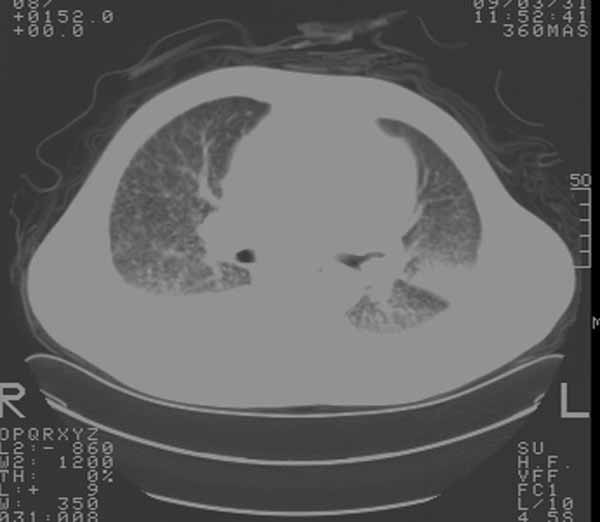

以下是引用余辉在2009-3-31 18:43:00的发言:[br]肺水肿,双侧心腔积液,心包积液,心影增大,疑似心衰

以下是引用wangyong1977在2009-3-31 20:46:00的发言:[br]肺水肿,双侧胸腔积液,心包积液,心影增大,疑似心衰 [br]

以下是引用宇宙ct在2009-3-31 18:57:00的发言:[br]肺水肿,双侧心腔积液,心包积液,心影增大,疑似心衰 [br] [br]